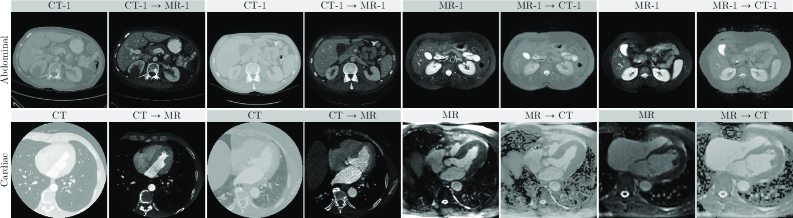

Refer to caption

Figure 4: Exemplary abdominal (row 1) and cardiac (row 2) images are shown before (cols: 1, 3, 5, 7) and after (cols: 2, 4, 6, 8) applying the proposed Semantic-aware Random Convolution (SRC). Image contrast was adjusted for better visualization.